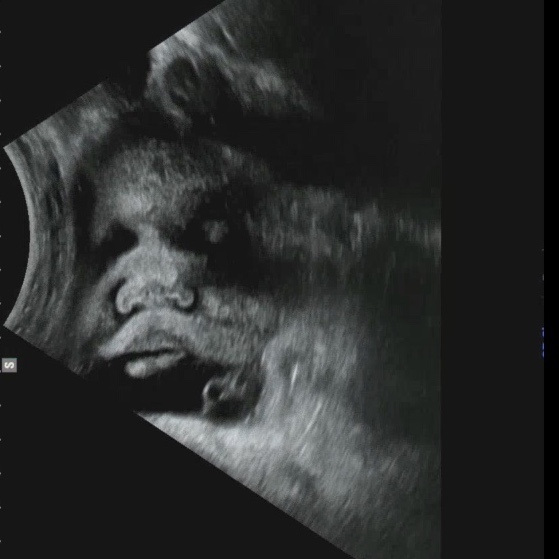

[임신일기] ~37주차 균검사결과, 첫내진, 자분제왕결정

<~37주차 증상> - 화요일부터 갑자기 아랫배가 스르르 아프면서 아기가 움직일때마다 태동이 크게 느...